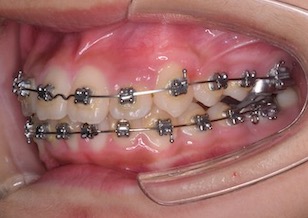

After Ⅰの写真は、左側上顎犬歯を牽引・移動中の口腔内写真です。